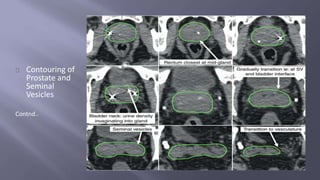

Contouring of

Prostate and

Seminal

Vesicles

Contnd..

Contouring of Prostate and Seminal Vesicles

Contouring of Prostateand Seminal Vesicles Contnd..